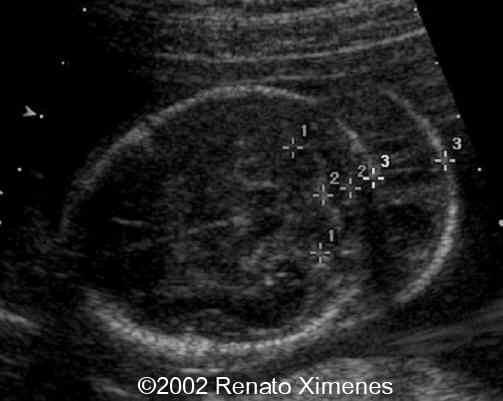

This second trimester fetus demonstrates a very thick nuchal edema with cystic hygroma:

case0072-1

case0072-2